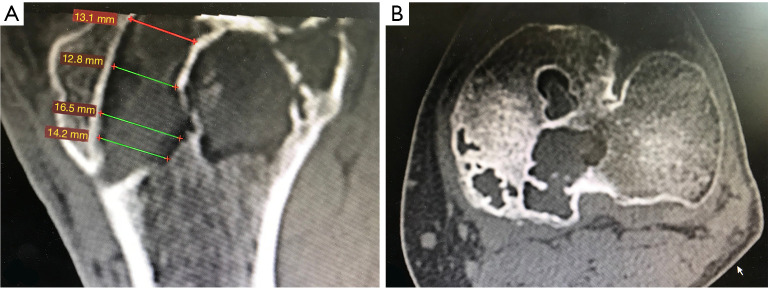

Abstract Image